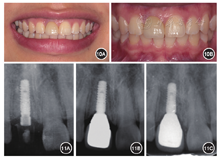

术后2个月复查示前牙牙龈缘高度协调,但11临时冠略宽于21,根据诊断蜡型制作导板对21行美学树脂修复改形。术后4个月复查牙龈健康,龈缘高度对称合适,牙齿宽长比正常(图8)。制取个性化印模,制作11氧化锆个性化基台和牙冠,完成最终修复(图9)。

本病例采用全程种植导板引导操作,并在术前设计制作临时修复体,保证后期螺丝固位,避免粘接剂残留可能引起的并发症[5]。术后即刻修复可在种植体骨整合同期实现对牙龈软组织的塑形。术后分析可见实际植入的种植体颈部整体稍偏远中0.47 mm,根部稍偏舌侧0.45 mm,均显著低于文献报道的平均误差(颈部1.07 mm,根部1.63 mm)[6]。植入窄颈种植体可尽量减少种植体占位进而保证充足的种植体周围成骨空间。Romeo等[7]对窄颈种植体进行了1~7年的临床和影像学纵向研究后发现,窄颈种植体与常规种植体的预后相似。本病例术后9个月回访可见骨量及骨边缘稳定,提示患者预后良好。

本文详细介绍了1例前牙区种植修复病例,在病例选择、治疗方案的确定及实施方面,体现了作者正确的临床思维及规范的临床操作;作者恰当地运用了位点保存和数字化导板等技术进行治疗,取得了良好的治疗结果,可以给读者启迪和帮助。当然,如果能观察更长的时间,文章就更有说服力了,因为前牙区种植修复的美学风险较高。另外,病例还有一些不足之处,比如最终修复体的颜色不够理想,目前的技术可以做得更好;而且邻牙用部分瓷贴面修复比树脂修复效果更好。